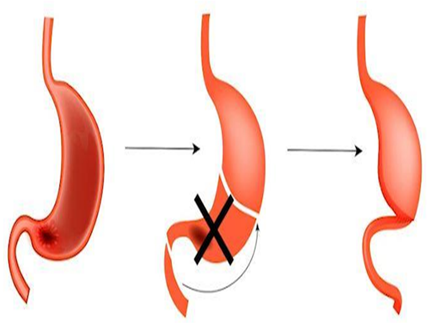

На начальных стадиях в первую очередь проводится операция по удалению участка, поражённого онкологией. Раньше часто проводилось удаление 2/3 желудка или полное удаление желудка. В последнее время благодаря диагностированию рака желудка на более ранних стадиях, когда образование ещё достаточно маленькое, стали более часто удалять приблизительно только половину желудка.

[Изображение 2] Удаление области желудка, поражённого раком |